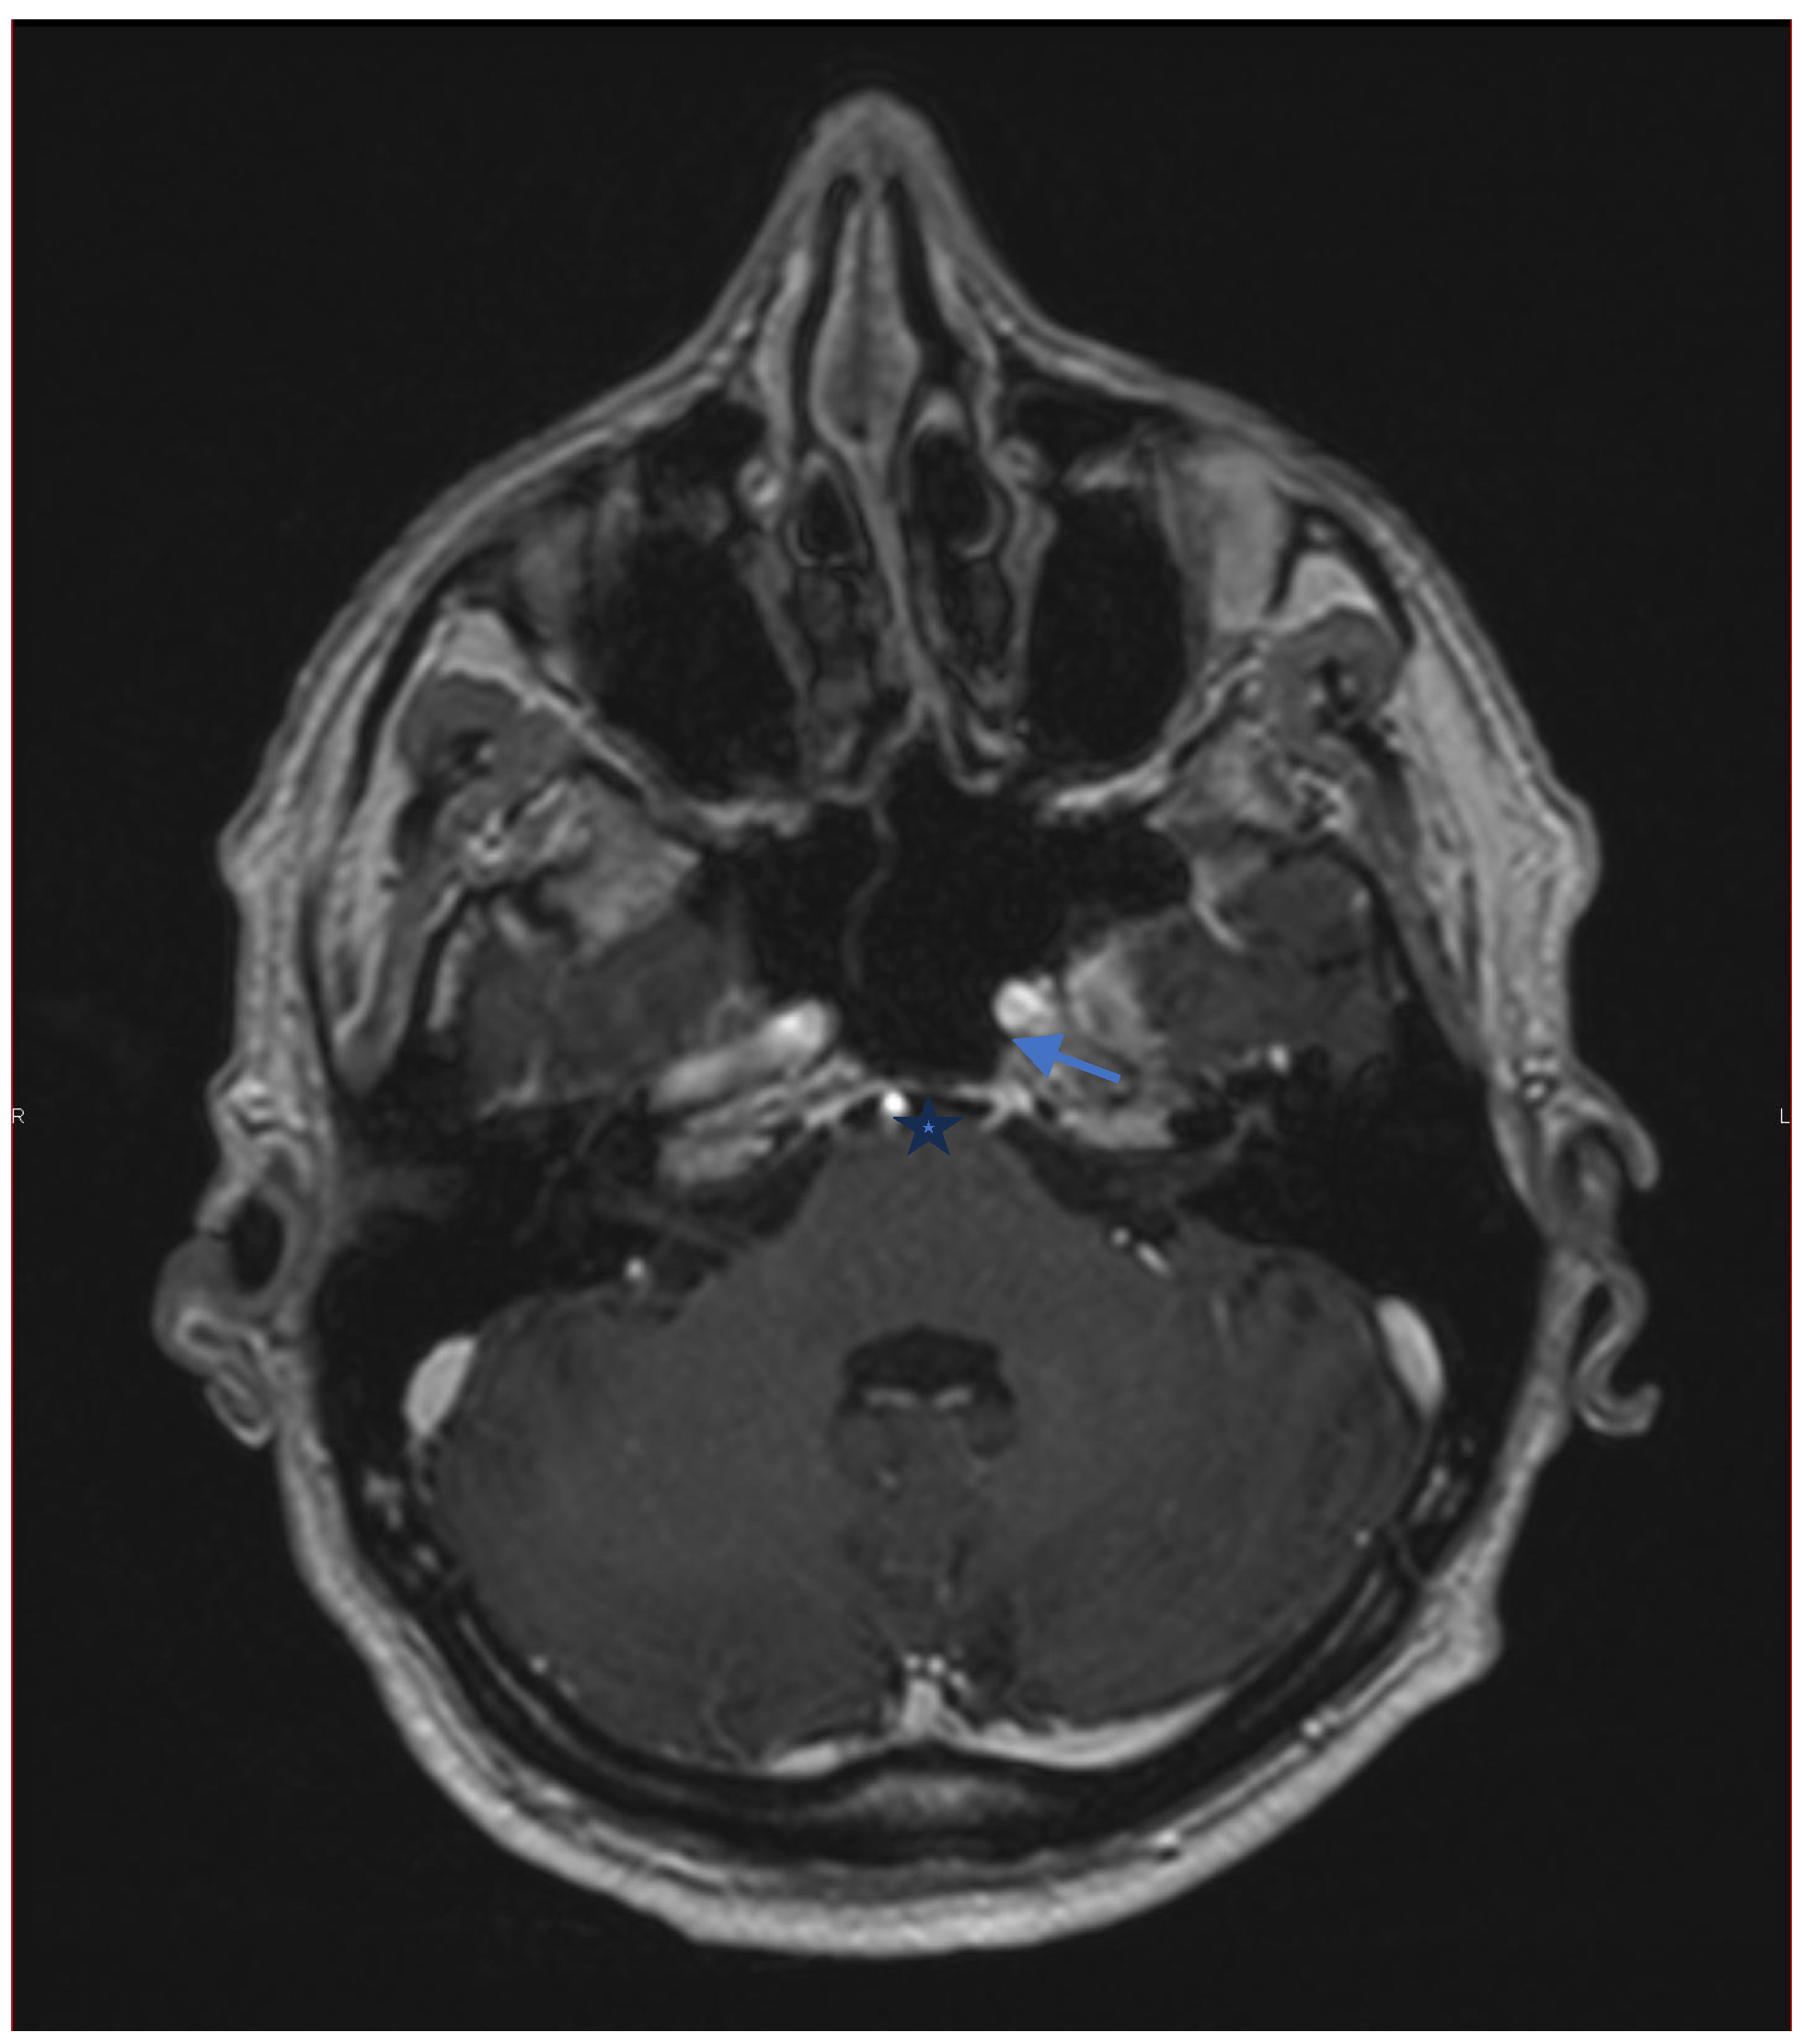

A review of the brain MRI was requested, focusing on the region between the pons and the petro-clinoid ligament. Imaging revealed signs of neuritis of the left sixth cranial nerve. The seventh cranial nerve could not be clearly visualized (Figure 6).

Neuroimaging is recommended in patients with an atypical clinical presentation, age under 50 years, or persistent symptoms beyond three months to rule out compressive, inflammatory, or demyelinating lesions. Brain MRI with gadolinium is preferred, as it can detect small enhancing lesions of individual cranial nerves [10]. Computed tomography of the orbits and skull base may also be considered if bone or sinus pathology is suspected. In our case, MRI ruled out a demyelinating disorder related to TNF-α inhibitor therapy. Careful review of the gadolinium-enhanced images showed neuritis affecting the sixth cranial nerve.

Figure 6. Axial T1 with gadolinium MRI focused on the region of the pons. The arrow shows the emergence of the enhanced sixth left cranial nerve. The star shows the pons.